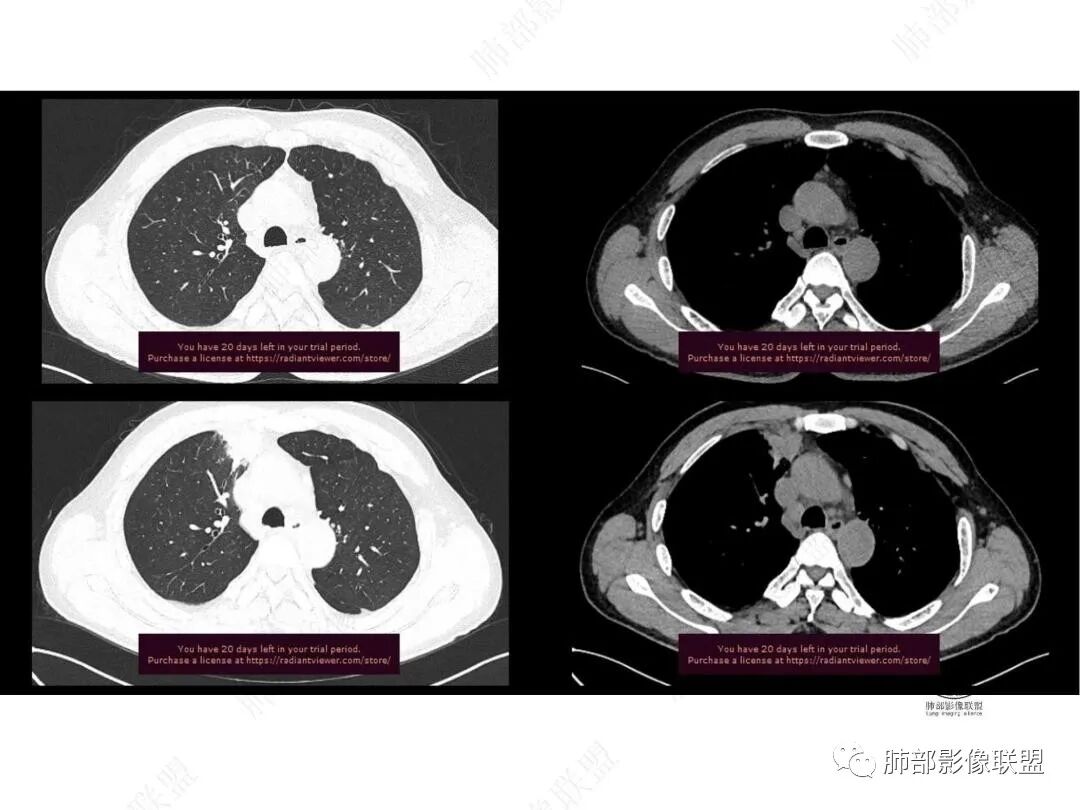

平扫图像

增强图像

右上叶前段胸膜下新发病灶;纵隔淋巴结较前增大

边缘平直,有锯齿状影

支气管进入其中,中近端堵

远端见斑片状高密度影

强化与肌肉类似,纵隔淋巴结强化类似

与胸膜关系:糊墙

1.中年男性,临床发热,症状较轻,中长病程,炎性指标轻度增高。

2.右肺上叶纵隔旁新发实性密度病灶,密度均匀,轻度强化,未见空洞、液化坏死及钙化,血管穿行自如,支气管进入后狭窄截止。灶周磨玻璃影边界不清,病灶未见明显分叶毛刺,平直、轻度收缩、周围偶见结节影,但未见树芽征。注意纵隔胸膜侵入或突入比较明确。纵隔淋巴结轻度增大。